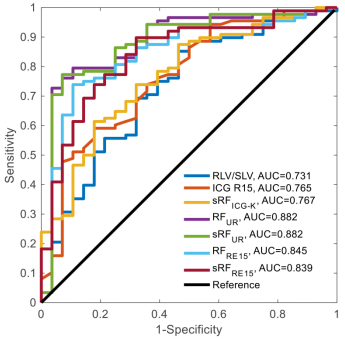

统计分析结果表明,本研究中提出的剩余肝脏功能参数RFUR(ml/min)和RFRE15(ml)在肝衰和非肝衰患者组之间具有显著性差异;在预测术后肝衰方面,RFUR(ml/min)和RFRE15(ml)具有更大的曲线下面积(AUC),分别达到了0.882和0.845,均优于传统的基于RLV/SLV或ICG的肝脏功能评估方法(图2,RLV/SLV:0.731,ICG R15:0.765,RFICG-K:0.767);多变量逻辑回归的结果表示RFUR (ml/min)和RFRE15(ml)是术后肝衰的独立预测因子。本研究验证了肝切除术前,使用肝胆特异性造影剂Gd-EOB-DTPA增强磁共振扫描序列,量化评估肝癌患者剩余部分肝脏功能的可行性,以及其预测术后肝衰的能力,提出的量化技术明显优于临床现有方法,使肝切除术前精确评估剩余肝脏功能体积成为可能,可与现有影像后处理平台整合。

图2 各参数预测术后肝衰的ROC曲线与AUC比较